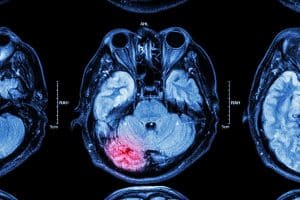

Vicens-Segura suffered from brain bleeding, a blood clot in the brain, a C5/C6 herniated disc, and damaged nerves from his neck to his arms. Doctors had to perform a craniotomy to help get the blood out.